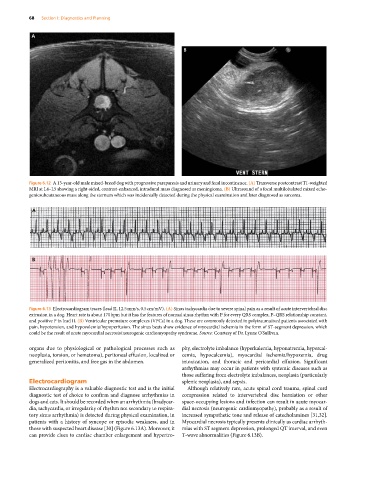

Figure 6.13 Electrocardiogram traces (lead II, 12.5 mm/s, 0.5 cm/mV). (A) Sinus tachycardia due to severe spinal pain as a result of acute intervertebral disc

extrusion in a dog. Heart rate is about 170 bpm but it has the features of normal sinus rhythm with P for every QRS complex, P–QRS relationship constant,

and positive P in lead II. (B) Ventricular premature complexes (VPCs) in a dog. These are commonly detected in polytraumatized patients associated with

pain, hypotension, and hypovolemia/hypoperfusion. The sinus beats show evidence of myocardial ischemia in the form of ST‐segment depression, which

could be the result of acute myocardial necrosis/neurogenic cardiomyopathy syndrome. Source: Courtesy of Dr. Lynne O’Sullivan.